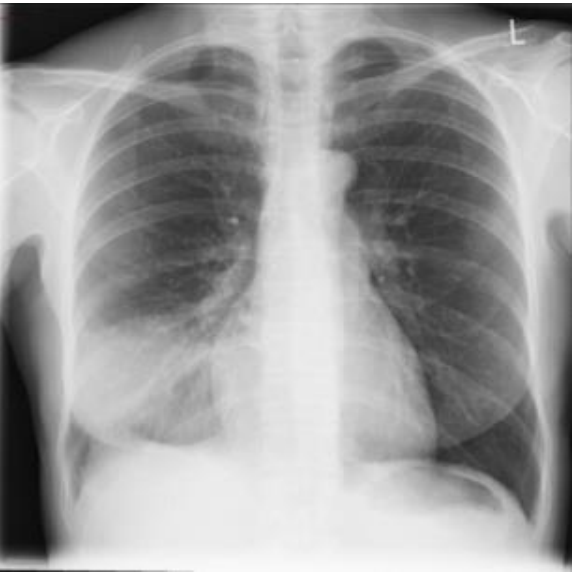

Mulher de 29 anos procura uma Unidade de Pronto Atendimento referindo, há dois dias, febre “alta”, de início súbito, acompanhada de tosse produtiva com expectoração amarelada e leve dor em terço médio de hemitórax direito, na inspiração profunda. Informa ter tido um quadro gripal poucos dias antes. Nega comorbidades, etilismo ou tabagismo. Contudo, relata ter tido um exantema maculopapular, no segundo dia de tratamento com amoxicilina, prescrita para um quadro de angina de evolução arrastada, na adolescência.

Ao exame: bom estado geral, embora abatida e com fácies de doença aguda. Corada, hidratada, anictérica, acianótica, eupneica. Ap Resp: MV universalmente audível, com estertoração crepitante em terço inferior à direita, onde se ausculta broncofonia. ACV, abdome e membros sem alterações. Sinais vitais: FC: 104 bpm; PA: 120/80 mmHg; FR: 20 irpm TAx: 39,0°C. Ao término do exame físico, foi submetida à radiografia de tórax, testes rápidos para Influenza e COVID-19 e coletada amostra de escarro para realização de bacterioscopia pelo método de Gram.

Os resultados evidenciaram:

Testes rápidos: COVID-19 – Negativo. / Influenza – Negativo.

Gram da amostra de escarro: No pequeno aumento, presença de mais de 50 neutrófilos/campo e menos de cinco células epiteliais/campo. No maior aumento (imersão), numerosos diplococos gram-positivos, vários deles intraleucocitários. Raros bastonetes gram-negativos exclusivamente extra-leucocitários.

A conduta terapêutica preconizada para essa paciente é